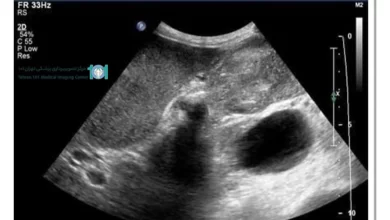

تصویربرداری تانسور انتشار DTI (Diffusion Tensor Imaging) یکی از فناوری های جدید در تصویربرداری پزشکی است. هدف این روش، تهیه یک نمای کلی اساسی و گسترده از مغز است به طوری که درک شهودی کاملی با استفاده از رنگ ها از نقاط قوت و ضعف تصویر ایجاد شود.

پس از تهیه تصاویر اولیه، مدل تانسور قابلیت شبیه سازی اطلاعات سه بعدی فیبرهای عصبی در هر واکسل را فراهم می کند. در نتیجه این فرآیند یک بازسازی سه بعدی (3D) و قابل درک و تفسیر ایجاد می شود.